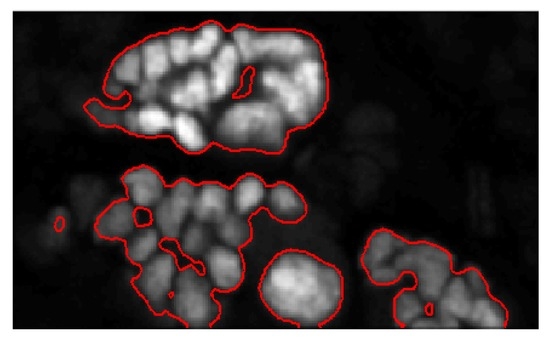

4.4. Seed Detection and Watershed

5.1. Evaluation on Sample Dataset